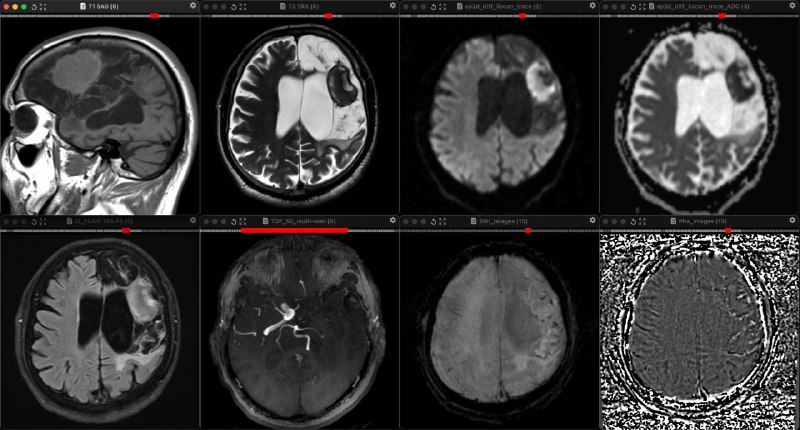

Второй раз в жизни вижу: массивный инфаркт с геморрагической трансформацией полтора года назад, из-за окклюзии левой внутренней сонной артерии. Массивная энцефаломаляция в бассейнах левых передней и средней мозговых артерий, и посреди этого грубого кистозного глиоза - почти идеально шаровидная хроническая инкапсулированная гематома. Внутри неё смесь производных гемоглобина, в центре растворимых и без клеток (гемихром, чуть-чуть, видимо, гемосидерин, немного, раз чуть гипер на т1 есть, внеклеточный метгемоглобин), но чёрный сигнал на Т2 объясняется не производными гемоглобина (иначе сигнал бы был низким и на SWI, чего мы не наблюдаем), а высоким содержанием белка. То есть, парадоксальным образом, время Т2 - короткое (отсюда низкий сигнал на T2W), а время Т2* - относительно длинное! То есть, в центре гематомы - белок, что приводит к черноте на Т2, как бывает, например, в белковых кистах кармана Ратке или почек, но эффекта магнитной восприимчивости с выпадением сигнала на SWI нет! Точнее, он есть, но только в капсуле, где, закономерно, в хронической гематоме всегда есть гемосидерин.

Такая гематома образуется, потому что вокруг в грубой энцефаломаляции, практически, нет кровообращения и, соответственно, механизм рассасывания гематомы отсутствует.

Да, и диффузия поэтому истинно ограничена, потому что содержимое, как желе: густое и вязкое.

Вы спросите: "А как отличить от абсцесса?" По сути, только по черноте на Т2 и по отсутствию клиники абсцесса. Но тёмным на Т2 абсцесс быть может, по той же причине - много белка и короткое Т2. Получается, что только по отсутствию клиники.

Видали такое раньше?

P.S. В первом подобном случае клиники инфекции тоже не было, и гематома оставалась стабильной на протяжении нескольких лет наблюдения. А картина была идентичной.